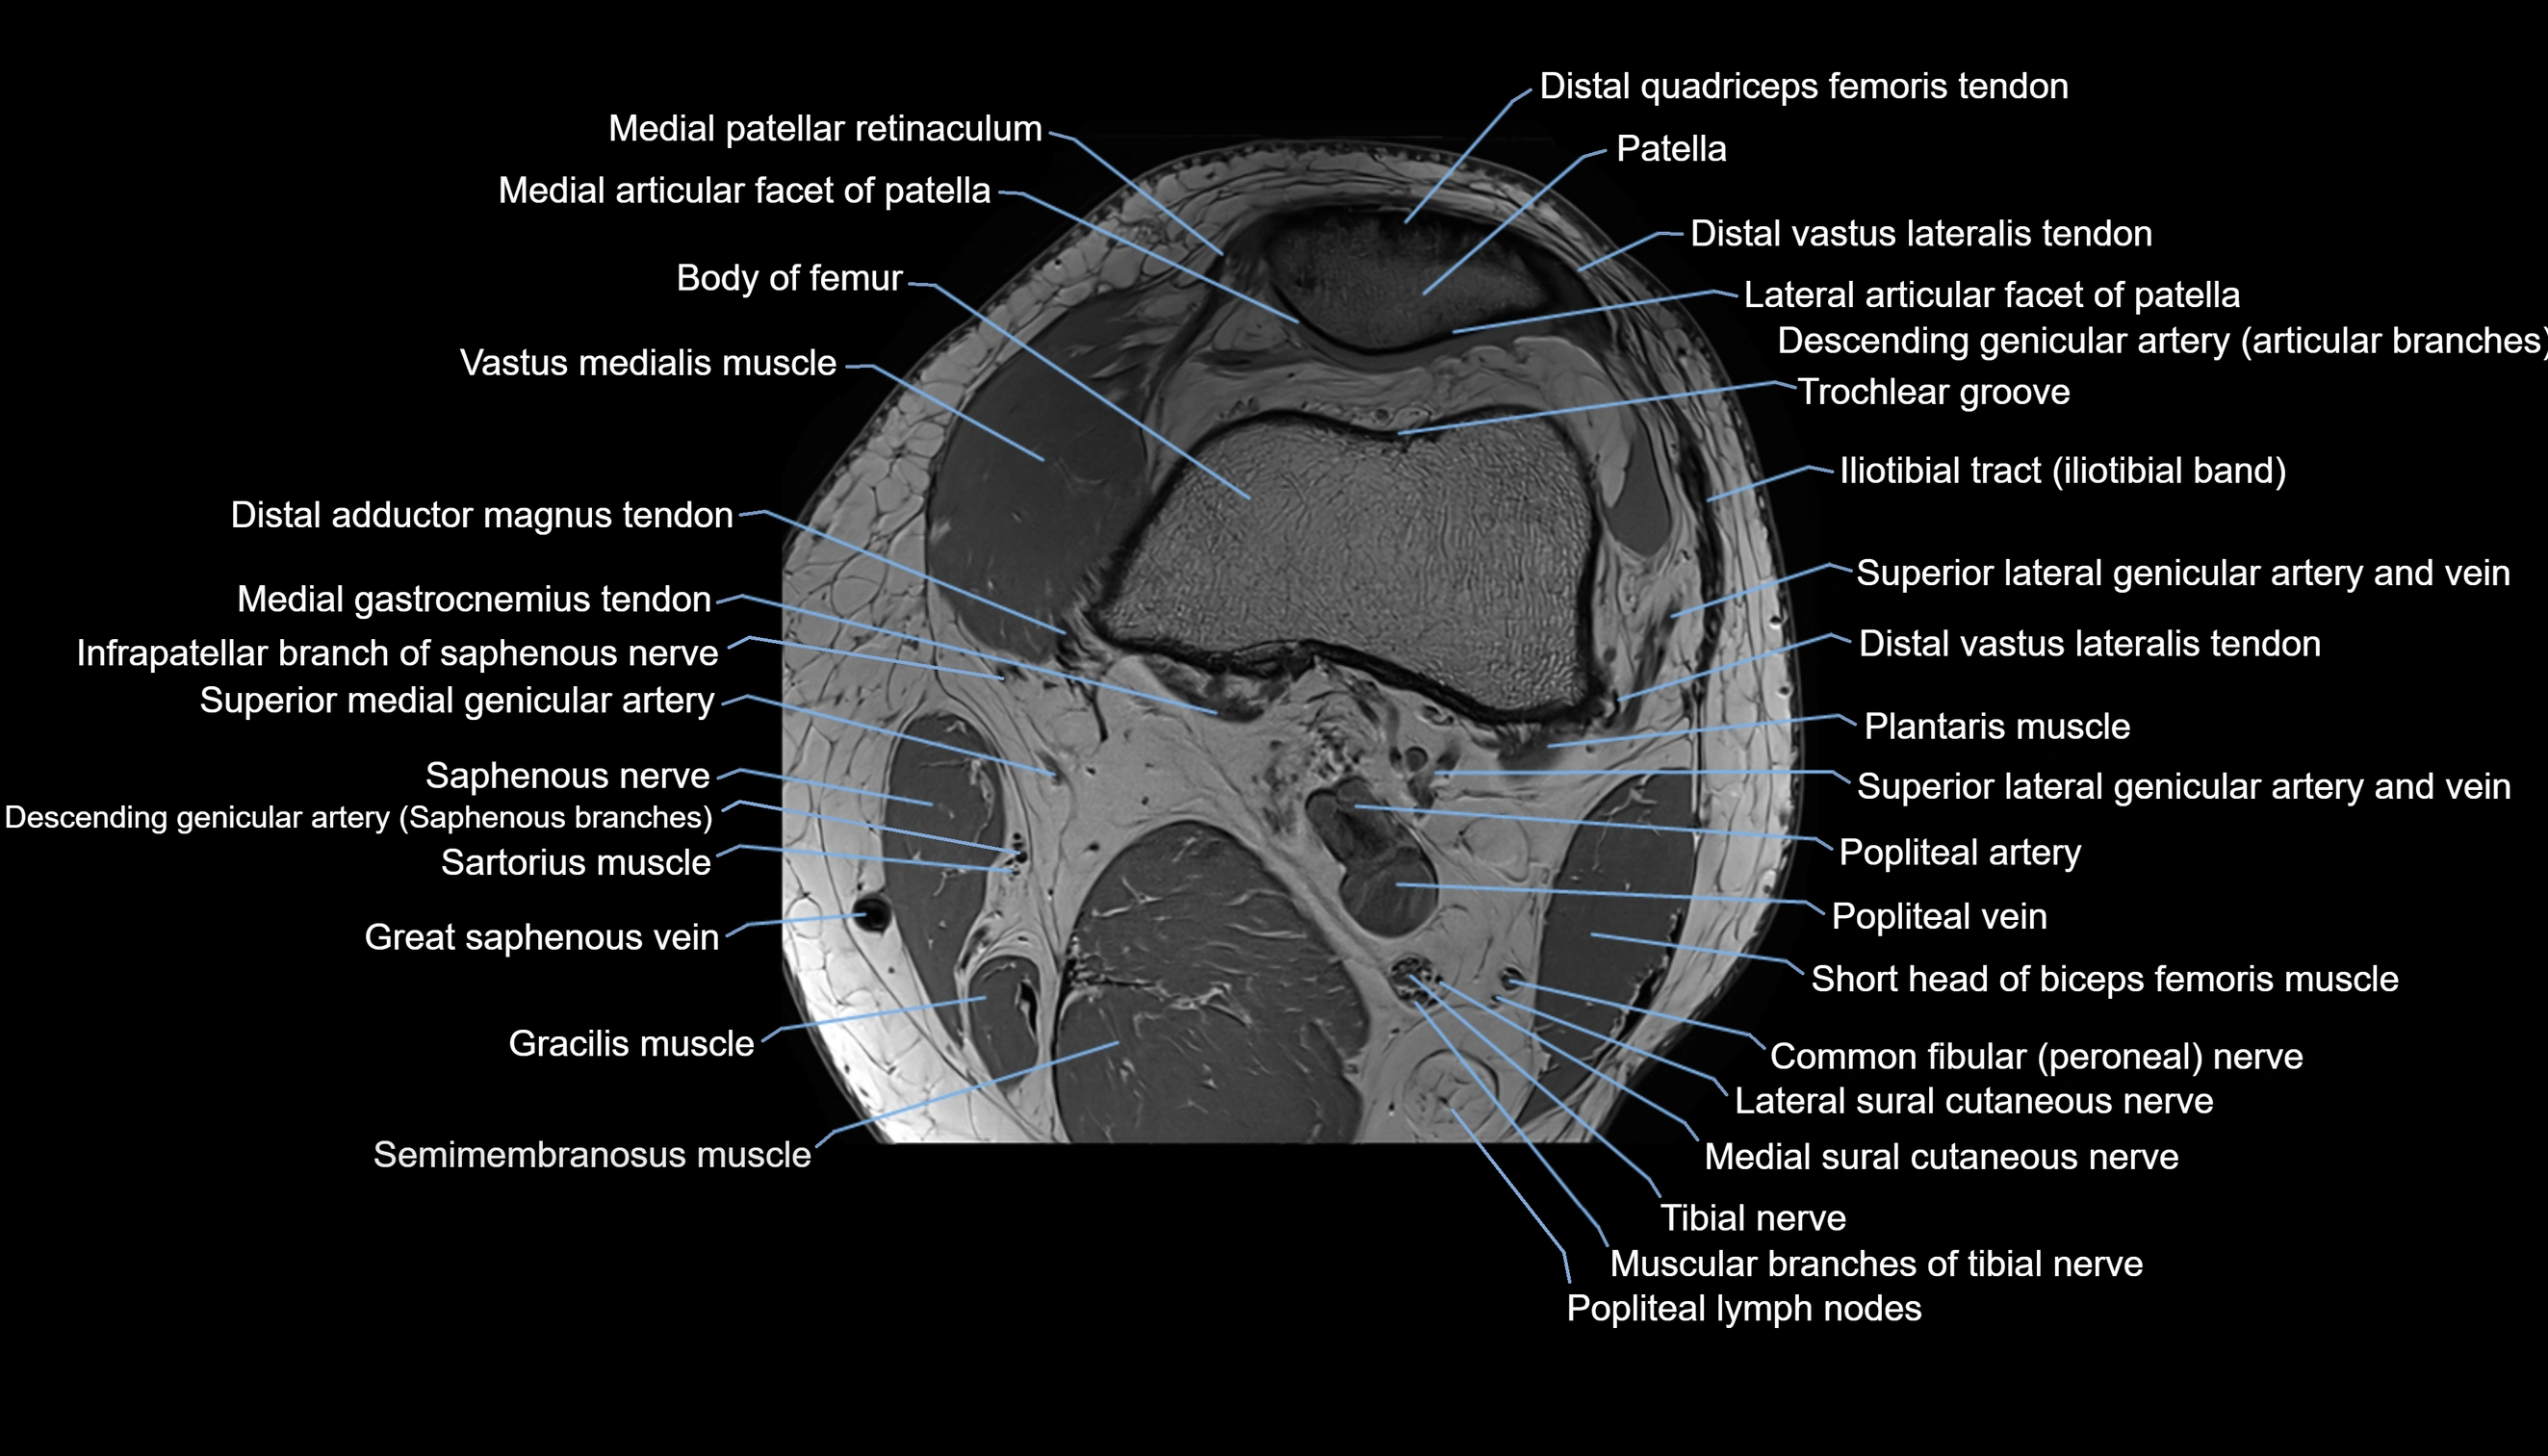

- Knee Joint

- Distal adductor magnus tendon

- Distal quadriceps femoris tendon

- Distal vastus lateralis tendon

- Distal vastus medialis tendon

- Lateral articular facet of patella

- Lateral condyle of femur

- Lateral gastrocnemius tendon

- Lateral head of gastrocnemius muscle

- Lateral patellar retinaculum

- Medial articular facet of patella

- Medial gastrocnemius tendon

- Medial head of gastrocnemius muscle

- Medial patellar retinaculum

- Medial sural cutaneous nerve

- Muscular branches of tibial nerve

- Patella

- Plantaris muscle

- Popliteal artery

- Popliteal lymph nodes

- Popliteal vein

- Sartorius muscle

- Semimembranosus muscle

- Trochlear groove

- Vastus Lateralis Obliquus Muscle

- Vastus medialis muscle

- great saphenous vein